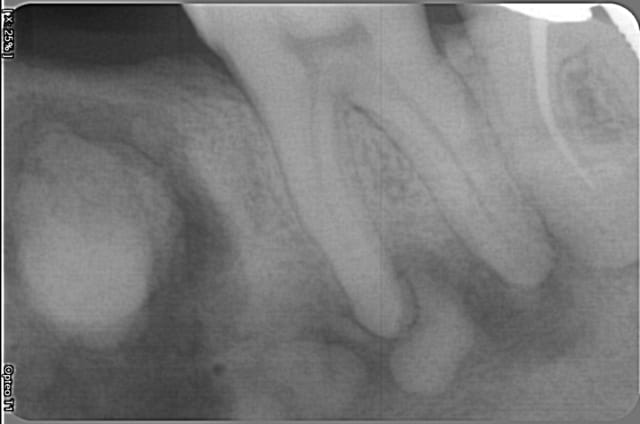

Patiente de 50 ans en bonne santé.

37 vivante.

Ostéome ?

Ca pourrait ressembler à une dysplasie cémento-osseuse floride vu l'atteinte du secteur 4. Au niveau du secteur 3 on pourrait également penser à un cémentoblastome.

Ce serait bien de faire un scanner puis de virer la grosse patate (qui semble présenter un liseré inflammatoire) afin d'avoir un retour d'histologie. Les formations apicales je n'y toucherais pas. La patiente est-elle d'origine africaine ?

pareil mais je dirais une sorte de DCF modérée.

Oui la patiente est africaine.

C'est donc à priori bénin ?

A priori ca ressemble à une DCOF (Cf ton article).

Cependant, tu n'es sur de rien, le diagnostic différentiel doit potentiellement se faire avec un cémentoblastome ou encore une ostéite condensante notamment secteur 3. La lésion présentant un halo inflammatoire important.

Donc oui, moi je ferais un scanner pour mieux objectiver l'image, contrôler l'intégrité des corticales.